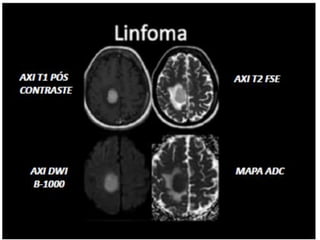

 AX T2 FLAIR

 AX T2 PROPELLER

 AX DIFUSÃO

 SWI

 AX T1+C

DIFUSÃO (DWI)

• Estudo do movimento

browniano.

• Restrições de fluxo arterial.

• Utilizado pra casos de AVC e

AIT.